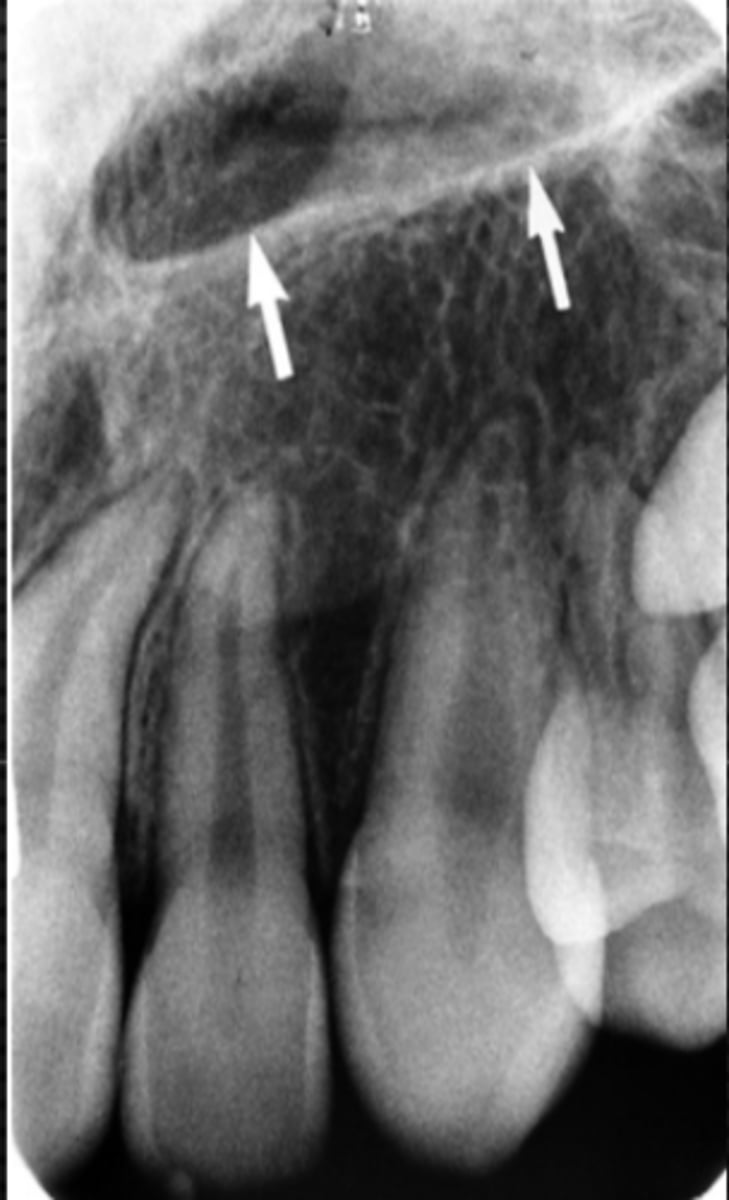

New cards

Black arrow - Floor of the nasal cavity

White arrow- maxillary sinus

Identify the structures

Maxillary sinus

Identify the structure